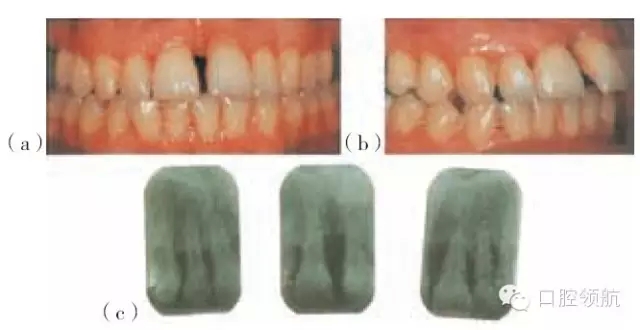

圖29.4 (a~c)有局限型侵襲性牙周炎病史的28歲的女性患者(不吸煙),之前進(jìn)行過(guò)牙周治療,左上中切牙及左下側(cè)切牙有炎癥。左下中切牙已有移位,不在牙弓的正?;【€(xiàn)內(nèi),出現(xiàn)傾斜及旋轉(zhuǎn)

圖29.5 (a,d)圖29.4患者的X線(xiàn)片,咬合面的X線(xiàn)片顯示上頜第一磨牙遠(yuǎn)中及下頜左側(cè)

第二磨牙,有齦下牙石和牙槽骨吸收。(b,c,e,f)根尖片顯示右上側(cè)切牙,左上中切

牙及側(cè)切牙,左下側(cè)切牙有齦下牙石及牙槽骨吸收